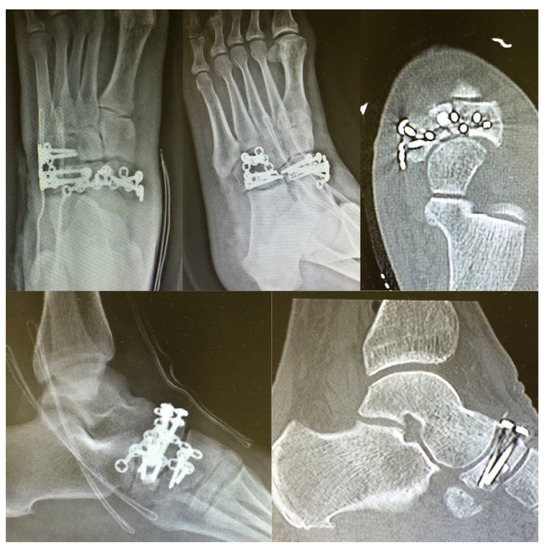

The Use of Low-Profile Angular-Stability Plates in a “Nutcracker” Tarsal Navicular Fracture Combined with a Cuboid Fracture: ORIF Experience

2. Case Presentation

3. Surgical Procedure